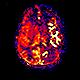

CT Perfusion with Diamox scan for Radiology- Before

How it works: CT perfusion with acetazolamide (Diamox) consists of a baseline CT perfusion scan of a portion of the brain, followed by injection of acetazolamide (a vasodilatory agent), and then a post acetazolamide CT perfusion scan of the same area. Normally, if blood flow to the brain is decreased, the vessels for that area will expand to maintain adequate oxygen flow, up to a maximum limit. The extent to which this can occur beyond baseline is the cerebrovascular reserve. CT Perfusion with acetazolamide allows assessment of the cerebrovascular reserve.

Equipment: Perfusion studies are usually performed on a Philips 64 or 256 channel CT scanner. OHSU is an ACR accredited CT facility.

Benefits: The study is used to evaluate cerebrovascular reserve, which can help determine the risk of future stroke. The study is often used to help determine which patients might benefit from interventions designed to increase blood flow beyond a very narrow or occluded vessel.

CT Perfusion with Diamox scan for Radiology- After